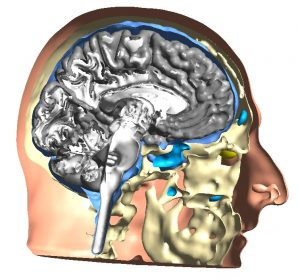

- Tworzenie na podstawie MRI pacjenta modelu 3D mózgu

Po zgromadzeniu dokładnego wywiadu medycznego oraz przeprowadzeniu odpowiednich testów( zalecenie niezbędne testów neuropsychologiczne, psychologiczne i badań np. EEG i QEEG) tworzona jest indywidualna diagnoza, która pozwala na doprecyzowanie potrzeb pacjenta. Opracowanie modelu 3D mózgu pacjenta na podstawie rezonansu magnetycznego głowy pacjenta pozwala na lepszą optymalizację stymulacji, co przekłada się bezpośrednio na zwiększenie skuteczności oraz na satysfakcjonujące efekty w terapii. Stymulacja terapeutyczna jest więc każdorazowo spersonalizowana i dostosowana do rodzaju schorzenia, budowy i funkcjonowania mózgu danego pacjenta.

Obliczeniowe modele mózgu pozwalają uchwycić specyficzną anatomię dla danego pacjenta.

To oparte na modelach spersonalizowane podejście do neuromodylacji stanowi podstawę do medycyny precyzyjnej z tCS, w której modele 3d są wykorzystywane do optymalizacji pól elektrycznych w poszczególnych obszarach zainteresowania tak aby zwiększyć bezpieczeństwo po przez dodawanie obszarów które ają zostać omineite i pole elektryczne nie będzie przez nie przechodizzć, oraz uzyskać bardziej skuteczne protokoły stymulacyjne. Przykładowo ustalamy pole tak aby omniać oczy albo obszar zajęty nowotworem. Do tworzenia takich modeli wykorzystujemy obrazy rezonansu magnetycznego T1 i T2 w odpowiednich do tego sekwencjach.

Model terapii stworzony w oparciu o wywiad medyczny, testy, a także zapis badania EEG pozwala z dużą precyzją wskazać obszary, które powinny być stymulowane, a także uniknąć niepotrzebnej stymulacji obszarów niepożądanych.

Jak powstaje model 3D mózgu pacjenta?

Neuroobrazowanie mózgu za pomocą rezonansu magnetycznego pozwala na wykonanie zdjęć mózgu pacjenta w różnych sekwencjach. Zaawansowane i specjalistycznie dostosowane neuroobrazowanie, na które kierujemy pacjenta przeprowadzane jest w Krakowie. Po uzyskaniu wyniku badania pacjenta, w naszej placówce Witold Tomasz z wykorzystaniem odpowiednich oprogramowań tworzy unikalny model 3D mózgu pacjenta.